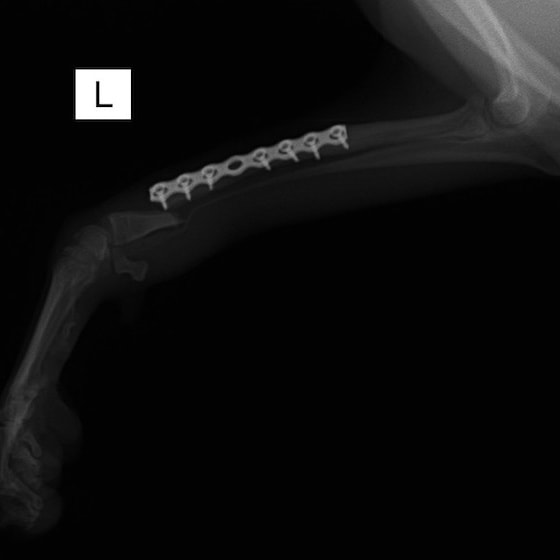

交通事故直後、胸腰部に激しい疼痛、両後肢に完全麻痺を認め、シェフシェリントン徴候を呈していました。レントゲン検査において、第11-12胸椎間の脱臼が認められました。

脊髄の減圧、脊柱管の再構築・安定化を目的に、片側椎弓切除術およびMatrixMANDIBLE Plateによる椎体固定を実施しました。

隣接椎体を架橋するようにプレートを設置しました。

術後レントゲン写真